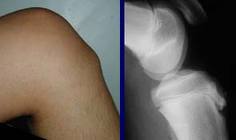

小孩膝生長板運動拉傷 中壢高正雄骨科復健診所

退化性關節炎 中壢高正雄骨科復健診所

膝蓋痛--半月板磨損了嗎? 中壢高正雄骨科復健診所